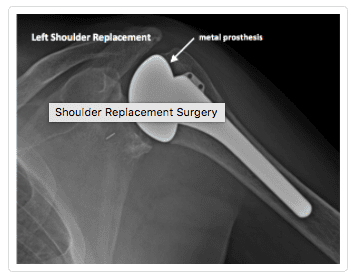

In this procedure, arthritic joint surfaces and the damaged ball-and-socket joint are replaced with artificial components. The ball is replaced with a metal ball that is secured into the arm bone (humerus) with a stem. The socket or glenoid is resurfaced for a smooth fit with a prosthetic made of high-density polyethylene. The shoulder replacement surgery is highly successful for the majority of patients, who experience pain relief and improved function.